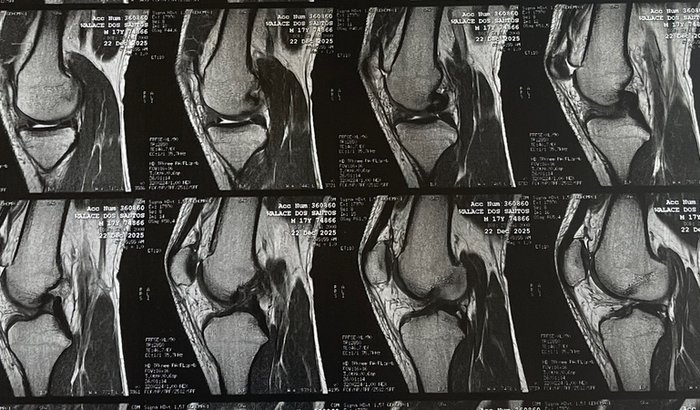

Depois de muitos anos vivendo o Jiu-Jitsu, treinando e competindo, acabei sofrendo uma lesão grave no joelho: rompimento do ligamento cruzado anterior e lesão no menisco. Para voltar a andar bem, treinar e lutar novamente, preciso passar por cirurgia.